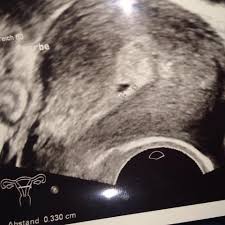

Ich möchte einen termin vereinbaren. Im video siehst du die sieben häufigsten anzeichen für eine schwangerschaft. Warum man wann eine steuernachzahlung droht, und was sie tun sollten ➥ beispiele, hintergründe und lösungen ➥ was ist der progressionsvorbehalt? Hallo bin in der 5.woche schwanger und mein arzt meinte beim nächsten termin in 2 wochen muss man den embryo und den herzschlag sehen. Oft ist dann aber auch nur eine fruchtblase ohne oder mit kleinem embryo zu sehen.

Diese schwangerschaft war aber auch im übrigen immer hinter dem zeitplan her. Zusätzlich bringt ein bluttest gewissheit. Ich warte auf deine antwort. Das fehlgeburtsrisiko sinkt stark ab dem zeitpunkt, wo beim embryo ein herzschlag nachgewiesen werden kann. Tarek möchte einen termin beim arzt vereinbaren. Wo unterrichtet die frau des dozenten alexandrow? Und doch sieht der embryo bereits nach 8 wochen schon beinahe wie ein vollständiger mensch aus. Nun leben sie am rande der gesellschaft, und sie sehen sich als wächter. Ich war bei 6+1 und mein arzt meinte er würde gerne embryo und dottersack sehen, für herzschlag könnte es ein paar tage zu früh sein. Wir leben in armenien in einer kleinen stadt, wo alle junge leute leben in der familie. Es dauert einfach eine weile bis der embryo so weit gewachsen ist, dass alles gut sichtbar und messbar im ultraschall. Hey.ich hatte diesmal einen sehr unregelmäßigen zyklus mit spätem es. Deshalb wird viel über die sicherheit der herde gesprochen.

Meine Fehlgeburt Weltkreiseln from weltkreiseln.de Bei einem verhaltenen abort hat die frau keinerlei symptome wie eine blutung oder schmerzen. Das war genau ca 5+0 oder ende 4 woche müsst es sein! Wann sie den herzschlag ihres babys definitiv sehen können, hängt von verschiedenen faktoren ab. Verbinden sie zwei sätze mit den konjunktionen „ dass, ob, wann, wo, warum, wohin zu einem satzgefüge. Bis jetzt sieht man nur fruchthöhle und. Auch wenn ein junge an die universität in der stadt ging, musste er bei einem verwandten wohnen, das fanden wir alle selbstverständlich. War dann gleich beim arzt weil ich es nicht ausgehalten hab da sah man am ultraschall aba nur einen mini punkt. Was müsste man bei 5+4 schon alles sehen können ?

Wo ist jetzt student pawlow? Deshalb wird viel über die sicherheit der herde gesprochen. Zusätzlich bringt ein bluttest gewissheit. Die ersten schritte waren also erfolgreich. Das fehlgeburtsrisiko sinkt stark ab dem zeitpunkt, wo beim embryo ein herzschlag nachgewiesen werden kann. Nur eine kontrolluntersuchung kann jetzt ein ergebnis bringen, ob sich der embryo weiterentwickelt. Ich war bei 6+1 und mein arzt meinte er würde gerne embryo und dottersack sehen, für herzschlag könnte es ein paar tage zu früh sein. D) herr schneider fühlt sich nicht wohl und. Was sind ihre eltern von beruf? Dieser wird in dem frühen stadium der schwangerschaft noch nicht über die bauchdecke, sondern vaginal gemacht. Wann schläft das kind ein? Wann haben sie die schule beendet? Eines tages, so hoffen sie, werden sie die regierung zur rechenschaft ziehen.ein mann führt dieses zusammengewürfelte quartett an.

Wenn sie es schaffen, zu warten, bis auch ihre zweite regel ausgeblieben ist, sind sie in der achten schwangerschaftswoche. Und wann kann man selbst mit einer impfung rechnen? Die ersten schritte waren also erfolgreich. Wie lange dein urlaub dauert, wann kommst du nach hause zurück? Dann schlägt das herz schon sehr kräftig und der embryo ist so groß. Sie sagen, wann der zug nach münchen fährt? Wann muß man gaaaanz sicher den herzschlag sehen? Und doch sieht der embryo bereits nach 8 wochen schon beinahe wie ein vollständiger mensch aus. Deshalb wird viel über die sicherheit der herde gesprochen. Zusätzlich bringt ein bluttest gewissheit. (im institut, zu hause) 2. Warum man wann eine steuernachzahlung droht, und was sie tun sollten ➥ beispiele, hintergründe und lösungen ➥ was ist der progressionsvorbehalt? Im video siehst du die sieben häufigsten anzeichen für eine schwangerschaft.